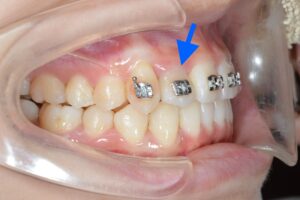

実際にオーバーコレクションステージを使うとどんな動きをするのでしょうか?

青がNo.8の歯並び、白がNo.11の歯並びです。

上下とも前歯がギュッと下がっていますね。

No.8の時点で余分な隙間がなければ、オーバーコレクションステージは使わなくて良いのですが、通常のアライナーと違いがあるのか気になるので使ってみたいなぁと思っています!